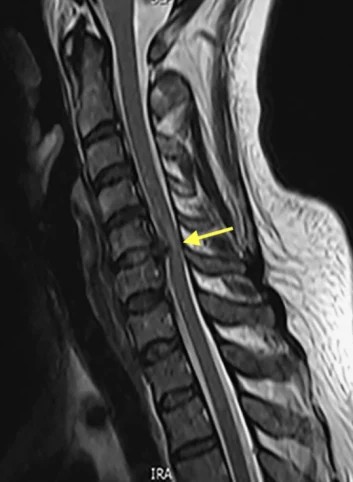

목디스크: 뼈 사이의 추간판(디스크)이 밀려나와 신경을 직접 압박하는 상태입니다. 이는 단순한 자세 문제를 넘어 구조적인 손상이 발생한 단계입니다.

1️⃣ X-ray 검사: 목뼈의 정렬 상태와 일자목/거북목의 진행 정도를 파악합니다.

2️⃣ 신경학적 검사: 저림 증상의 위치를 통해 몇 번 디스크에 문제가 있는지 예측합니다.